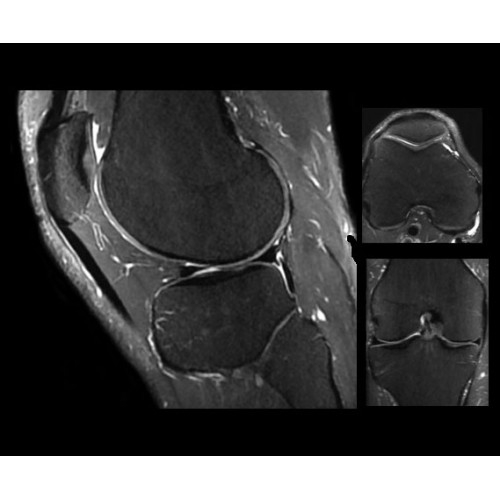

SIGNA PET/MR 3.0T — это гибридная система, в которой совмещаются две принципиально разные технологии — магнитно-резонансную томографию (МРТ) и позитронно-эмиссионную томографию (ПЭТ). Система отличающийся высокой чувствительностью и эффективностью и предназначена для диагностики в области онкологии, неврологии, кардио-васкулярных исследований, исследований воспалительных процессов.

Компания GE Healthcare представляет революционную, полностью интегрированную систему SIGNA PET/MR1, в которой сочетаются времяпролетная технология (TOF) и возможности напряженности магнитного поля 3.0 Тл. Мы поможем вам поднять исследования на более высокий уровень. SIGNA PET/MR позволяет достичь впечатляющей точности и скорости исследований, а благодаря новейшей технологии реконструкции Q.Clear2 качество изображений улучшается в два раза. Кроме того, в систему включен полный набор клинических приложений и гибких катушек для проведения любых видов исследования, открывая для вас возможности визуализации, о которых вы даже не догадывались.

В систему SIGNA PET/MR встроены запатентованные детекторы кремниевого фотоумножителя (SiPM) и сверхчувствительные кристаллические сцинтилляторы на основе лютеция толщиной 25 мм. Благодаря этому обеспечивается исключительная чувствительность и возможность использования времяпролетной диагностики (TOF).

Кроме того, в результате использования технологии TOF и инновационной технологии реконструкции Q.Clear вы сможете добиться прекрасного соотношения сигнал/шум. А благодаря технологии нулевого времени эхо (ZTE) визуализировать костную структуру без ионизирующего излучения. Все эти разработки для улучшения качества сканирования и точности анализа помогут вам использовать весь потенциал ПЭТ/МРТ.